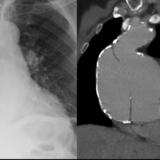

Aortic aneurysm

Date: 03/02/2014

Views: 2436